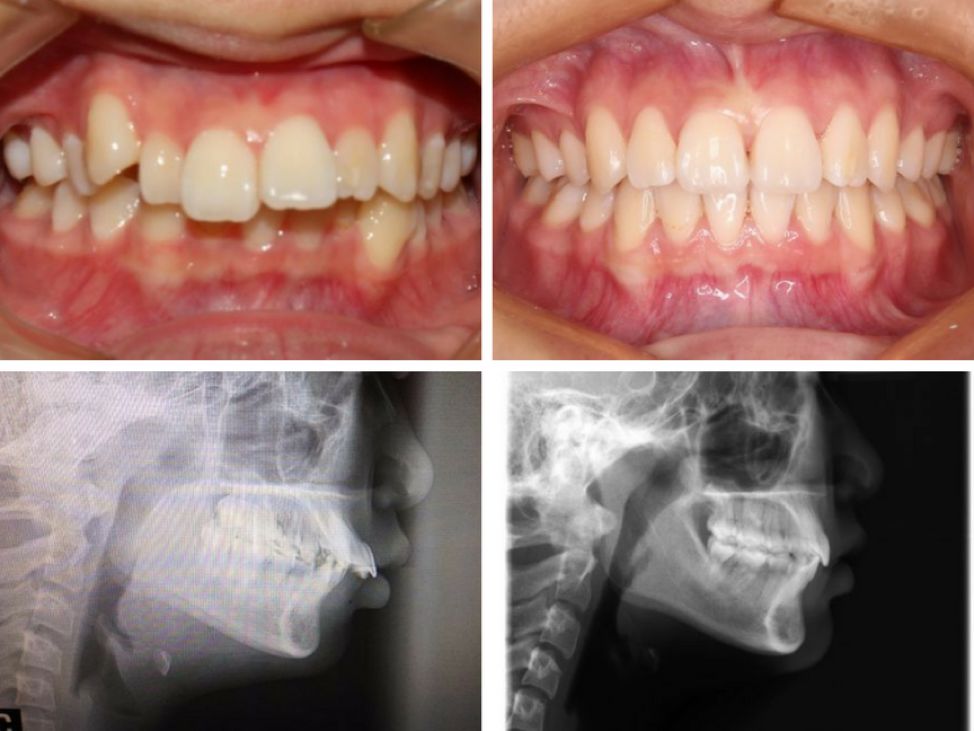

正面(阴影是整之前,白色是整之后)

侧面(阴影是整之前,白色是整之后)

1

2017/02 开始前

2

2017/06 三个月

左脸

4

现在

2017/08 五个月

3

右脸

正脸

张嘴笑

细心的观众们看出来我的变化了吗???

以前下庭太短,我加了辅助线让大家可以看得更清楚,我的人中和下巴都长了好多哦~